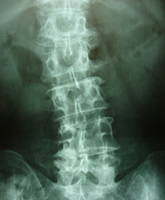

X線画像で診た肩こり・顎関節・肋椎関節・肩関節・頸部関節などの痛みと姿勢の関係

35年近く病院で呼吸器・循環器・消化器などと共に運動器(四肢・関節・体幹)等

検査し感じた事は皆様が思った以上年齢と共に骨・関節・内臓・血管までもが変形が進行しています。

ただし過度のスポーツや姿勢の異常で体に『負担を掛け過ぎると』軟骨や椎骨や各関節まで骨の変形が始まります。